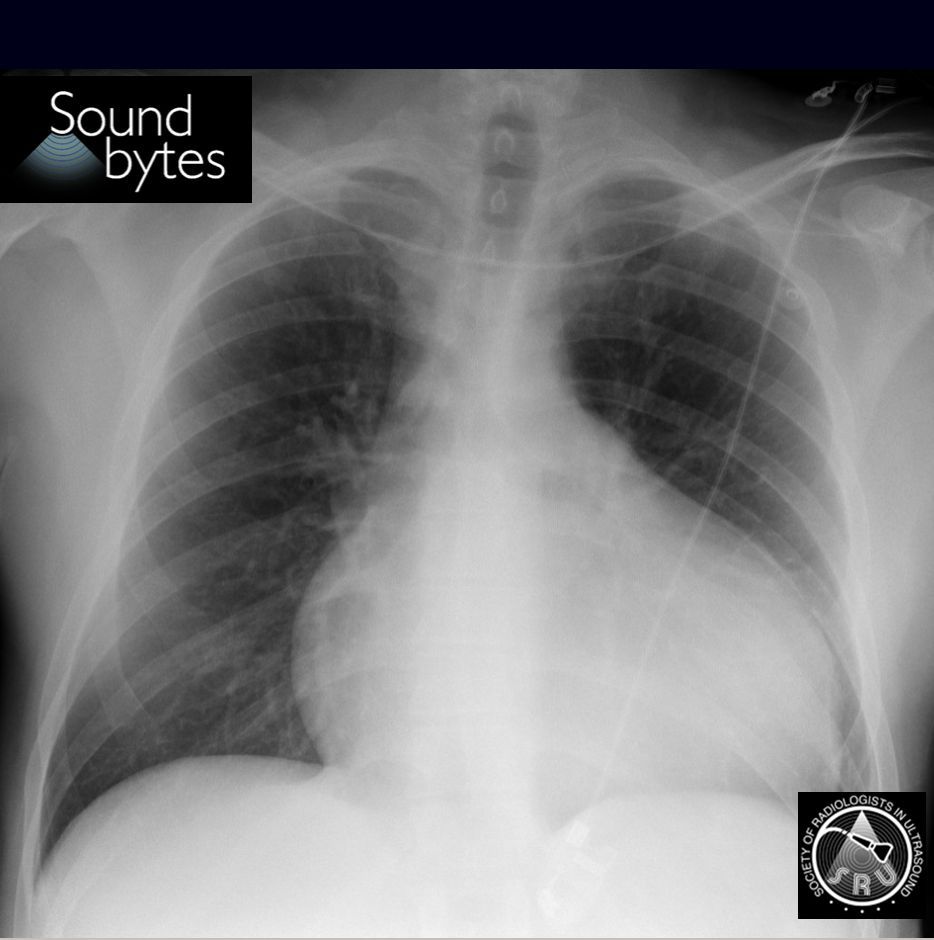

Dx: Cardiogenic congestive hepatopathy.

Findings: Gallbladder wall edema 2/2 liver congestion, dilated hepatic veins, and CXR showing cardiomegaly.

Case courtesy of Dr. Eugenio Zalaquett, Red de Salud UC-Christus, Santiago, Chile